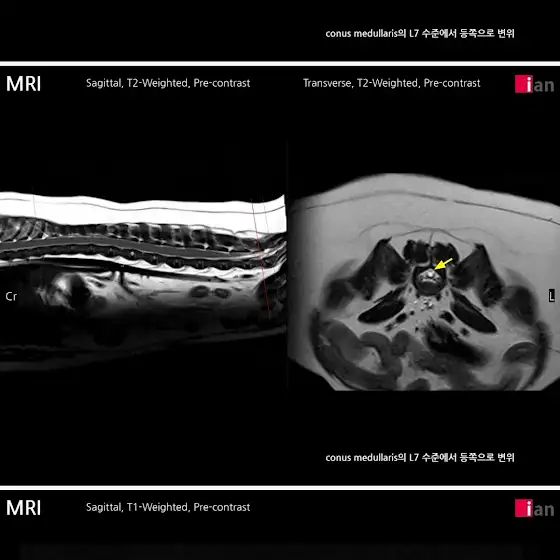

이 조그마한 녀석이 희귀병에 걸렸습니다

7번척추에 척수가 짧아서 아파합니다

서울대병원에서만 수술할수 있다네요

쓸개골도수술해줘야하는데 성장판이 안닫혀서 기다리다 이제야 닫혔다네요지금 쓸개골 4기가되어서 빨리해줘야하는데

일단 척추먼저 상담해보고 해야겠네요